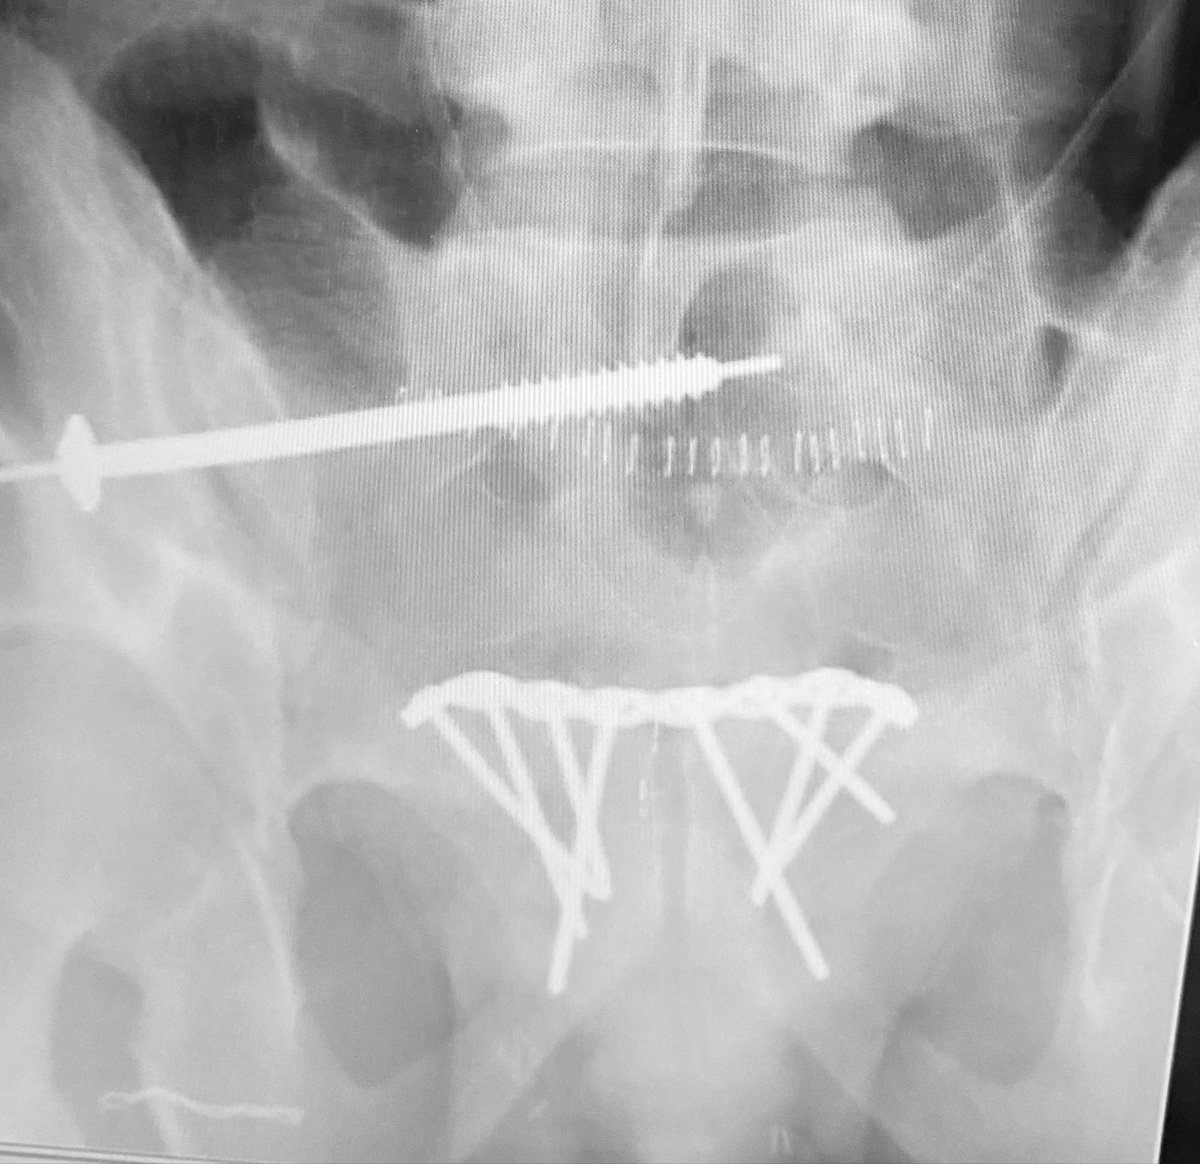

We added more fixation screws to the plate and removed the clamp - is the SI joint sufficiently indirectly reduced for lag screw compression? If so, how do you determine this? Or will this SI joint need ORIF?

We assess the SI indirect reduction to be essentially purely distracted based on numerous tangential images - we then used an upper sacral segment cannulated iliosacral lag screw over a washer to finally reduce/compress the injured SI joint

Additional fully threaded iliosacral screws were added within the safe osseus fixation pathways to further stabilize the posterior pelvic injury

The postop CT axial images reveal the indirect reduction quality and implant location details